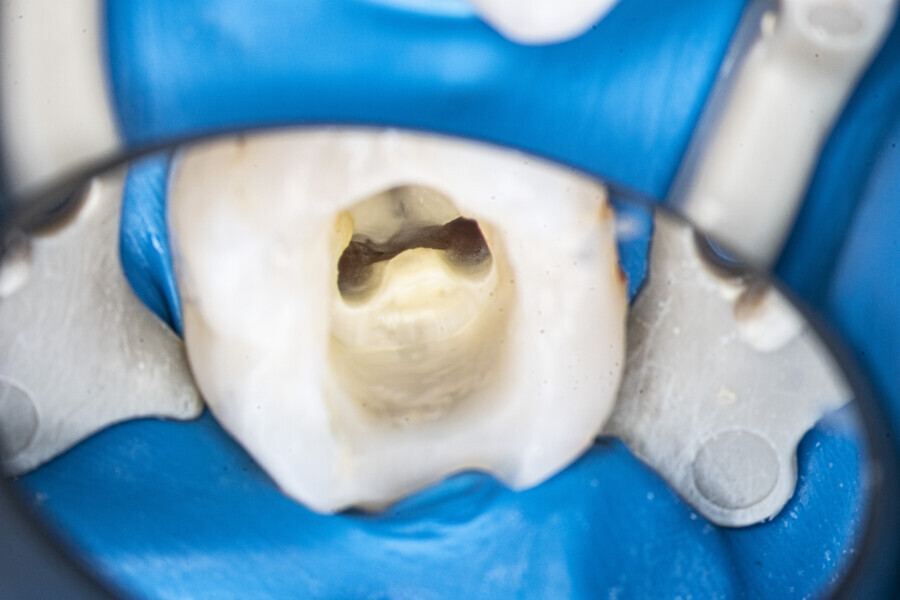

Case 3 (Figs. 37–46)

A 30-year-old female patient presented to the office owing to pain related to the maxillary right first molar. The radiograph revealed a periapical radiolucency, indicating exacerbated chronic periapical periodontitis. The access cavity was created with the Safe Access and Preparation Concept burs set (manufacturer). The pulp chamber was cleaned with 5.25% NaClO activated with the SkyPulse laser. Four orifices were located, and all four canals were shaped in the same sequence described previously. The LPE enhanced irrigation was performed with activation by the SkyPulse laser. In the mesial root, a clean isthmus was visible, and the irrigants started to flow between the MB1 and MB2 canals in the apical third, which was confirmed with a micro-suction cannula. In the MB1, MB2 and DB canals, apical preparation was performed with Endostar E3 Azure files (Poldent) up to size 25/0.04 owing to the apical curvatures. In the DB canal, patency was not established. The final irrigation protocol was performed in the same sequence as described before. The periapical radiograph confirmed that the isthmus was filled with the sealer.